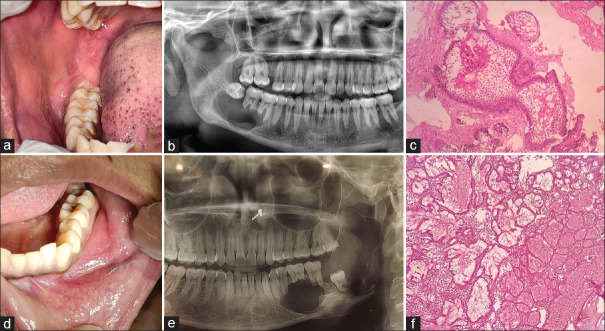

Introduction: A clear understanding of the biological nature, the importance of diagnosis and the identification of adjunct treatment options of ameloblastoma are gaining importance in their surgical planning and treatment. The anti-tumourigenic properties of alpha-tocopherol (Vitamin E) are significant and less studied among odontogenic tumours. Hence, the present study aimed to calculate and compare the mean Vitamin E levels in ameloblastoma patients and healthy controls.

Materials and methods: This observational case-control study included 24 participants (12 cases and 12 controls) and was conducted following institutional ethical approval. After obtaining the informed consent, blood samples were collected from the study participants. Serum Vitamin E levels were assessed using high-performance liquid chromatography and expressed in mg/mL.

Results: After the independent t-test, the mean serum Vitamin E of the case group was found to be lower (mean ± standard deviation [SD] = 5.28 ± 0.62 mg/L) when compared to healthy controls (mean ± SD = 12.08 ± 1.92 mg/L) (P ≤ 0.0001). The mean Vitamin E level of plexiform variant (5.2 mg/L) was less when compared to the follicular variant (6.02 mg/L) (P = 0.34) and plexiform ameloblastoma was more common among younger age groups (P = 0.01).

Discussion: The reduced concentration of Vitamin E among ameloblastoma cases can have a potential role in the pathogenesis and aggressiveness of odontogenic tumours. Among ameloblastoma, plexiform variant showed low mean serum Vitamin E. The therapeutic action of Vitamin E should be studied in detail for better adjunctive treatment options in ameloblastoma.